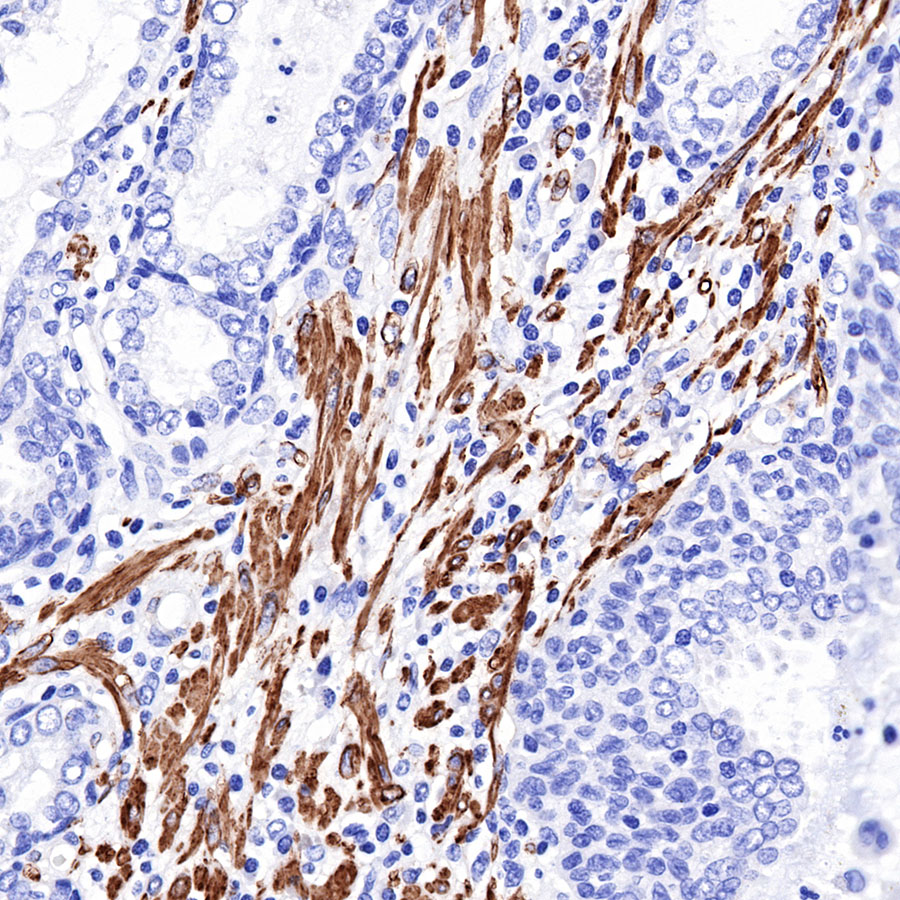

Immunohistochemistry